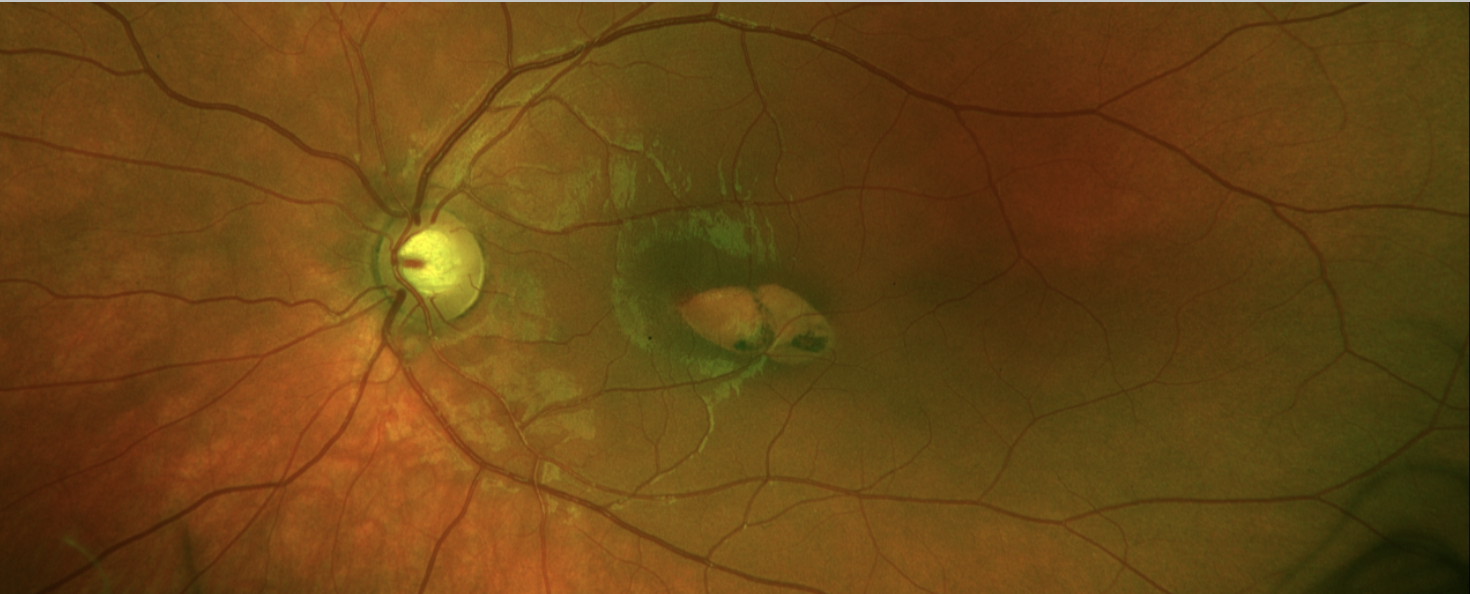

Abbildung 3: Arterienastverschluss des rechten Auges in der Fluoreszenzangiographie

Abbildung 4: Torpedo-Makulopathie